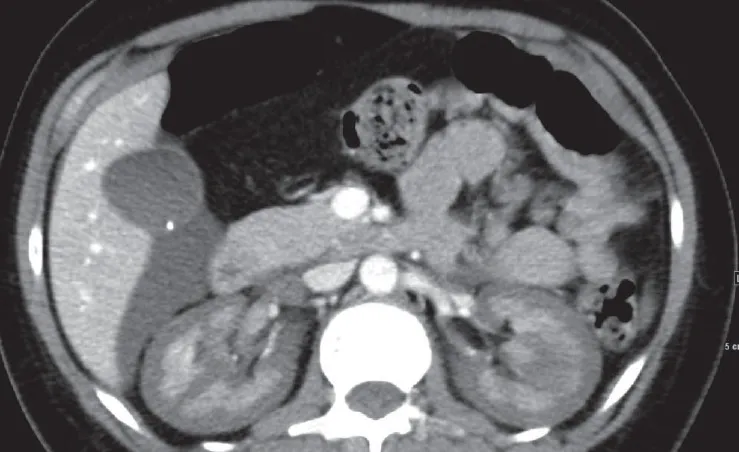

Uma causa incomum de hematúria glomerular intermitente!

Uma causa incomum de hematúria glomerular intermitente!

Hematúria pós infecção, caso clínicos para auxiliar no entendimento de causas glomerulares comuns e raras...